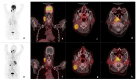

Materials and methods: In this prospective cross-sectional study, twenty-three (23) patients aged 52.9 ± 10.4 (19.6), 17 males and 6 females with primarily diagnosed (n = 17) or pre-treated (n = 6) SCC of the oral cavity (OCSCC, n = 11), oropharynx (OPSCC, n = 9), nasopharynx (NPSCC, n = 2) and unknown primary (n = 1) underwent imaging with [68Ga]Ga-Pentixafor-PET/CT. In 16/23 patients 2-[18F]fluoro-2-deoxy-D-glucose ([18F]F-FDG) served as a standard reference. All lesions were visually rated using a 5-point Likert scale. For both tracers, maximum standardized uptake values (SUVmax) and the total lesion uptake (TLU) were recorded and compared using the Wilcox-signed rank test. In addition, the tumor-to-background ratios were derived using the liver (TLR), spleen (TSR), and posterior cervical muscles (TMR) as background. The relationships between the SUVs of the two tracers were assessed using the Spearman correlation. CXCR4 immunohistochemistry (IHC) staining was correlated with 68Ga-Pentixafor-PET/CT in 21/23 patients.

Results: Ninety-one percent (21/23) of tumors were visually detected on [68Ga]Ga-Pentixafor; however, [68Ga]Ga-Pentixafor was less intense compared with [18F]F-FDG-PET. Quantitative analysis showed higher [18F]F-FDG SUVmax in comparison with [68Ga]Ga-Pentixafor (16 ± 6.7 vs. 5.8 ± 2.6 g/mL, p = 0.011) and SUVmean (9.3 ± 4.1 vs. 3± 1.6 g/mL, p < 0.001) and TBR 4.9 ± 2.3 vs. 2.36 ± 1.4 p = 0.014. Nasopharyngeal cancer demonstrated more intense tracer accumulation than oropharyngeal and oral cavity malignancies. CXCR4 IHC staining was positive in 15/21 patients, and there was a statistically significant correlation between IHC staining and [68Ga]Ga-Pentixafor SUVmean r = 0.5 p = 0.027, and performance status r = 0.83 p = 0.0104.

Conclusions: In conclusion, although [68Ga]Ga-Pentixafor cannot replace [18F]F-FDG as a diagnostic tool because of its lower avidity, the correlation between CXCR4 targeted 68Ga-Pentixafor PET imaging and CXCR4 IHC staining indicates the potential of 68Ga-Pentixafor as an effective tool for selecting patients who may benefit from therapies targeting CXCR4. In addition, [68Ga]Ga-Pentixafor has no physiological brown fat uptake, which often obscures cervical lesions on [18F]F-FDG PET/CT imaging.